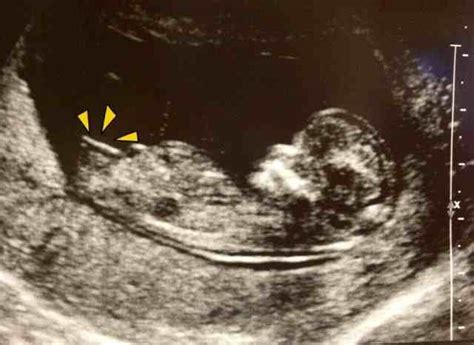

怀孕16周从b超单子上和唐氏筛查单子上能否看出是男孩还是女孩

您好,很高兴为您解答,B超当时在检查的时候是能看出来的,但是也是专业人士,非专业是看不出来的,另外唐氏筛查是排畸形的检查,是看不出男孩还是女孩的,不管是男孩还是女孩,健康最重要